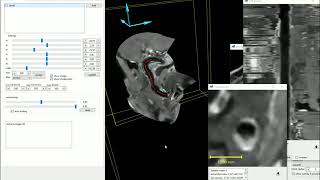

Direct vessel wall imaging (VWI) from dark blood MRI dataset video

Direct vessel wall imaging (VWI) from dark-blood MRI dataset

Direct vessel wall imaging (VWI) from dark-blood MRI dataset Vessel wall imaging using high resolution 3D CUBE T1 fat sat with MSDE and HyperSense

Direct vessel wall imaging (VWI) from dark-blood MRI dataset

Direct vessel wall imaging (VWI) from dark-blood MRI dataset Vessel wall imaging using high resolution 3D CUBE T1 fat sat with MSDE and HyperSense